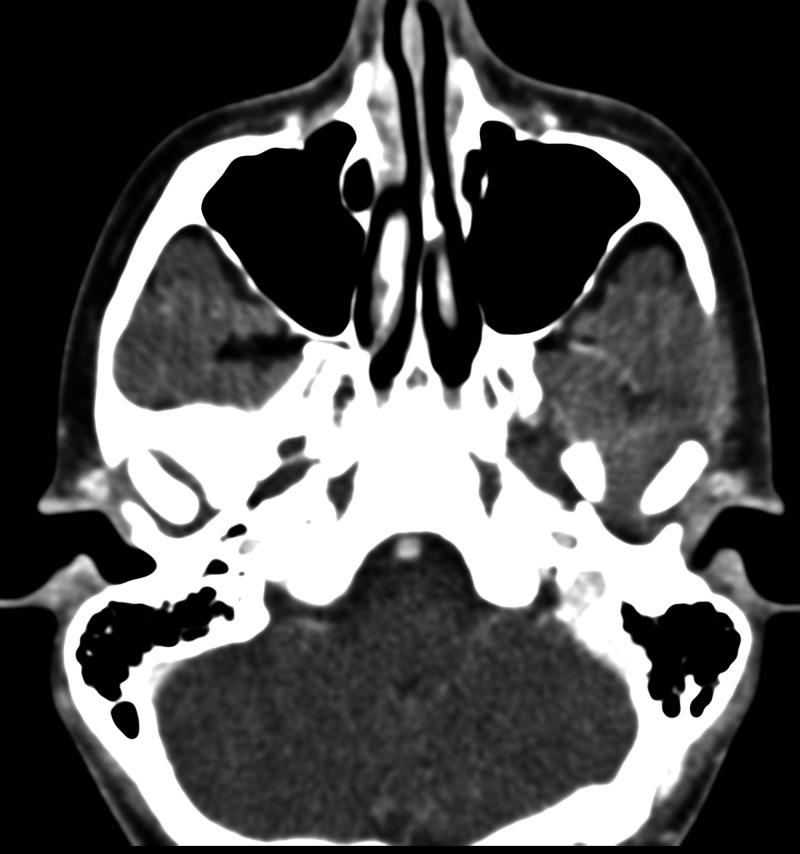

Idiopathic mandibular condylar resorption is a rare condition in which the mandibular condyle of the temporomandibular joint (TMJ) becomes resorbed and thus reduces in size and volume. This leads to TMJ dysfunction that commonly requires surgical correction; however, more conservative interventions can also be utilized. We present a case of idiopathic mandibular condyle resorption in a 17-year-old female presenting with TMJ pain and clicking with mastication. A definitive diagnosis of this condition ultimately requires imaging studies, a reliable option being magnetic resonance imaging (MRI), which will reveal erosion of the mandibular condylar process (often bilaterally) with diminished mass and volume leading to the known sequelae of symptoms.

特发性下颌髁突吸收是一种罕见的病症,其中颞下颌关节(TMJ)的下颌髁突会被吸收,从而尺寸和体积减小。这会导致颞下颌关节功能障碍,通常需要手术矫正;然而,也可以采用更保守的干预措施。我们报告一例17岁女性特发性下颌髁突吸收病例,该患者表现为颞下颌关节疼痛以及咀嚼时弹响。对这种病症的明确诊断最终需要影像学检查,可靠的选择是磁共振成像(MRI),它将显示下颌髁突的侵蚀(通常为双侧),伴有质量和体积减小,进而导致已知的一系列症状。